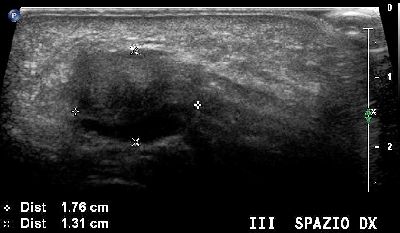

Neuroma di Hauser del secondo spazio intermetatarsale (img. 01) Neuroma Hauser 01